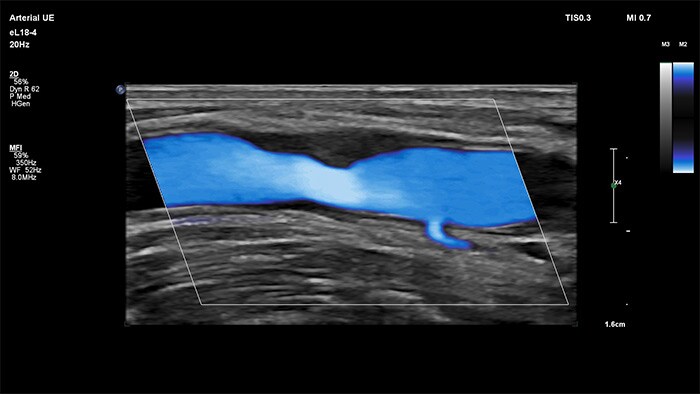

MicroFlow Imaging de Philips se ha diseñado para identificar con una extraordinaria sensibilidad las zonas anatómicas que presentan un flujo sanguíneo lento y débil en los tejidos y, además, mejora la resolución del flujo en las exploraciones vasculares. Gracias a su alta resolución y cantidad mínima de artefactos, los profesionales sanitarios pueden visualizar y caracterizar alteraciones sutiles en el flujo alrededor de la placa estenótica para así elaborar diagnósticos fiables.